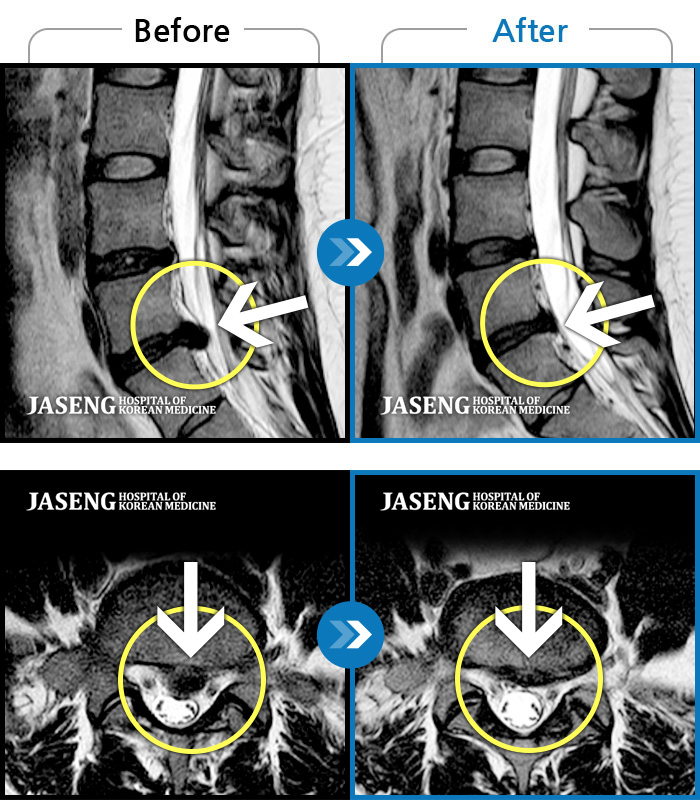

허리디스크

천안 · 김세정 원장

좌측 다리 저림이 매우 심해 야간통증 및 일상 생활에 제한이 많은 상태로 내원하였습니다.

촬영시기

2021.08.07 ~ 2024.07.22